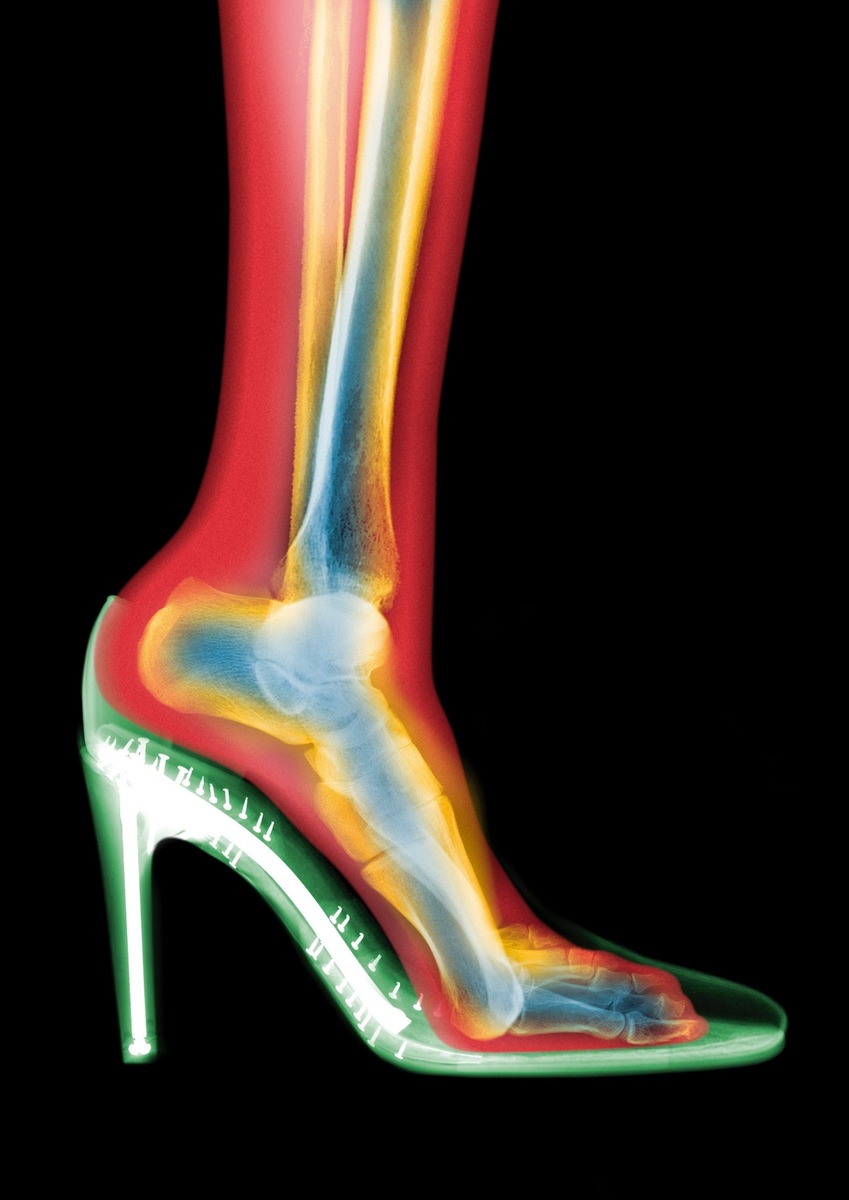

На цветном рентгеновском снимке в стиле МРТ видно, что туфли на шпильке приподнимают пятку и заставляют стопу наклоняться вниз. Из-за такого положения вес тела смещается вперёд, что меняет механику походки и увеличивает нагрузку на колени, бёдра и поясницу.Фотография Ника Визи, Научная фотобиблиотека